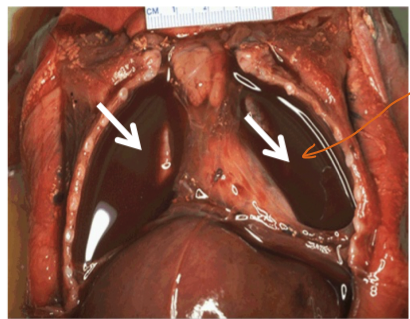

a. ) Name the type of effusion shown below

b. ) Name the components of the effusion

c. ) What could cause this condition in the lungs

a. Sero-sanguineous exudate/effusion

b. The components = serous fluid + blood

c. In the lungs this is often the result of primary or metastatic pleural tumours